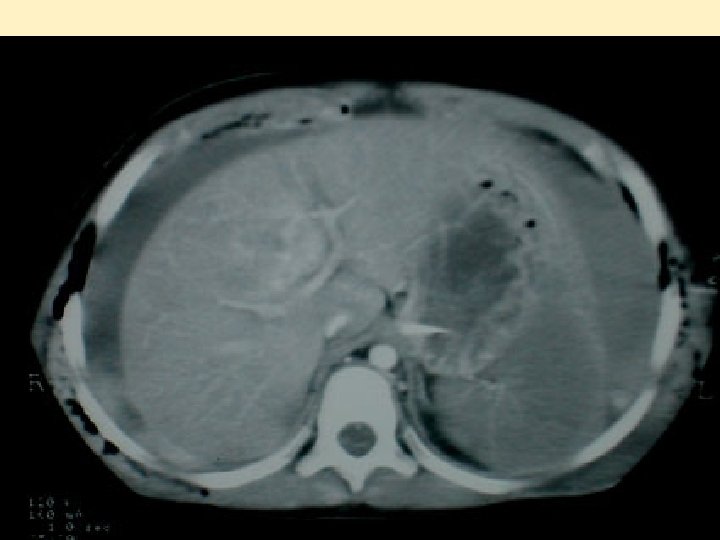

Lésions abdominales - Assez rares: 20 à 30% des lésions - Lacérations hépatiques et spléniques - Traitement conservateur en milieu spécialisé - Lésions de désinsertion: mésentère, reins - A évaluer et réévaluer : clinique trompeuse

ARBRE DECISIONNEL TRAUMA ABDOMINAL BOLUS 20 ML / KG EN 5' STABILITE TRANSITOIRE INSTABILITE PERSISTANTE STABLE BOLUS 20 ML / KG EN 5' TRAITEMENT CONSERVATEUR SURVEILLANCE EXPLORATIONS COMPLEMENTAIRES TRANSFUSION > 50 ML / KG Laparotomie après Exploration a minima